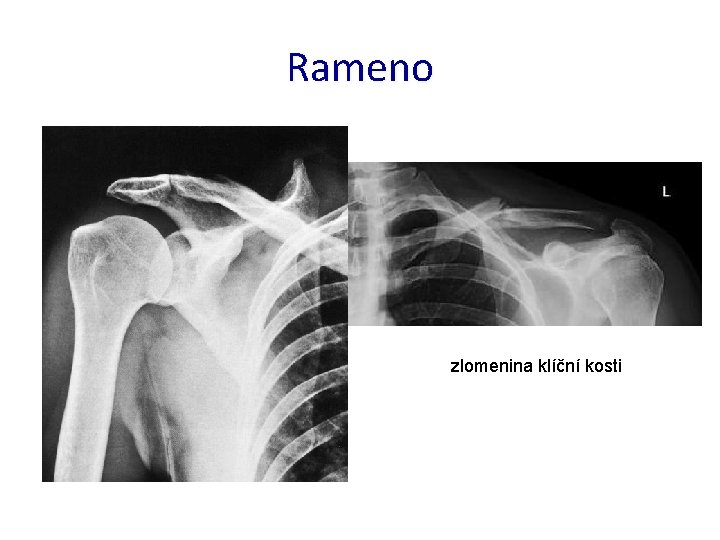

Rameno zlomenina klíční kosti